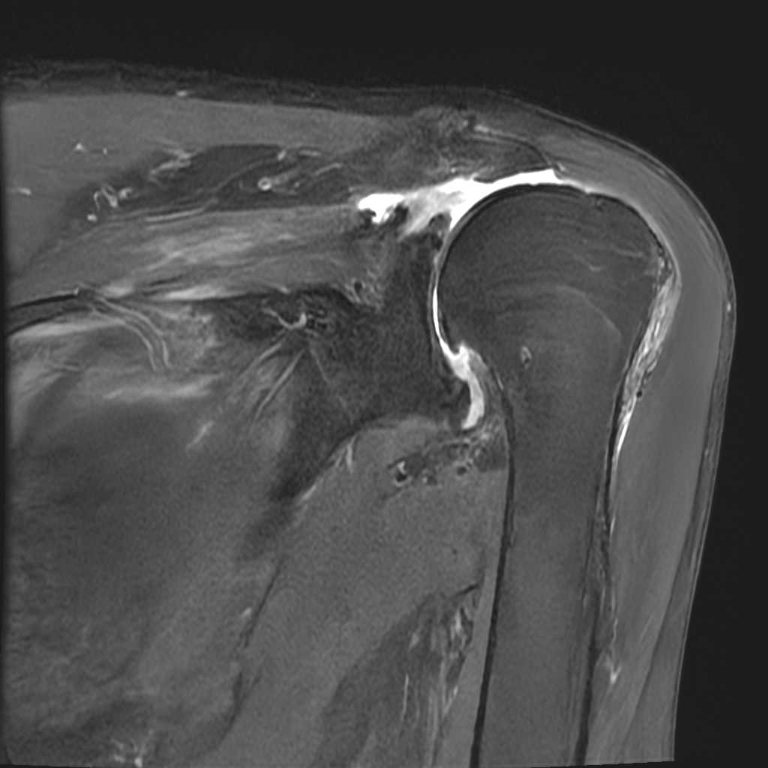

膝関節

腱板断裂